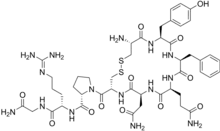

| Molecular structure of vasopressin. This hormone is related to Type A and Type B adipsia. | |

Adipsia, also known as hypodipsia, is a symptom of inappropriately decreased or absent feelings of thirst.[1][2] It involves an increased osmolality or concentration of solute in the urine, which stimulates secretion of antidiuretic hormone (ADH) from the hypothalamus to the kidneys. This causes the person to retain water and ultimately become unable to feel thirst. Due to its rarity, the disorder has not been the subject of many research studies.

Initial testing for adipsia involves electrolyte, blood urea nitrogen (BUN) and creatinine levels, serum and urine osmolality, blood hormone levels, like vasopressin (AVP). In patients who have defects in thirst regulation and vasopressin secretion, serum vasopressin levels are low or absent.[12] Measurements of urine electrolytes and osmolality are critical in determining the central, rather than renal, nature of the defect in water homeostasis. In adipsia, the fractional excretion of sodium is less than 1%, unless a coexisting defect in AVP secretion is present. In salt intoxication, the urine sodium concentrations are very high and fractional excretion of sodium is greater than 1%. Initial test results may be suggestive of diabetes insipidus. The circulating AVP levels tend to be high, which indicate an appropriate response of the pituitary to hyperosmolality. Patients may have mild stable elevations of serum sodium concentrations, along with elevations in both BUN and creatinine levels and in the BUN/creatinine ratio.[4]

Type A

Type A (essential hypernatremia syndrome) involves an increase of the level in which solvent molecules can pass through cell membranes (osmotic threshold) for vasopressin release and the activation of the feeling of thirst. This is the most characterized sub-type of adipsia, however there is no known cause for Type A adipsia. There is debate over whether osmoreceptor resetting could lead to the increase in threshold. Other studies have shown that it is the loss of osmoreceptors, not resetting, that cause the change in threshold.[13] Patients with Type A adipsia can be at risk of seizures if they rapidly re-hydrate or quickly add a significant amount of sodium into their bodies. If not treated, Type A adipsia could result in both a decrease in the size of the brain and bleeding in the brain.[11]

Type B

Type B adipsia occurs when vasopressin responses are at decreased levels in the presence of osmotic stimuli. Although minimal, there is still some secretion of AVP. This type may be due to some elimination of osmoreceptors.[13]